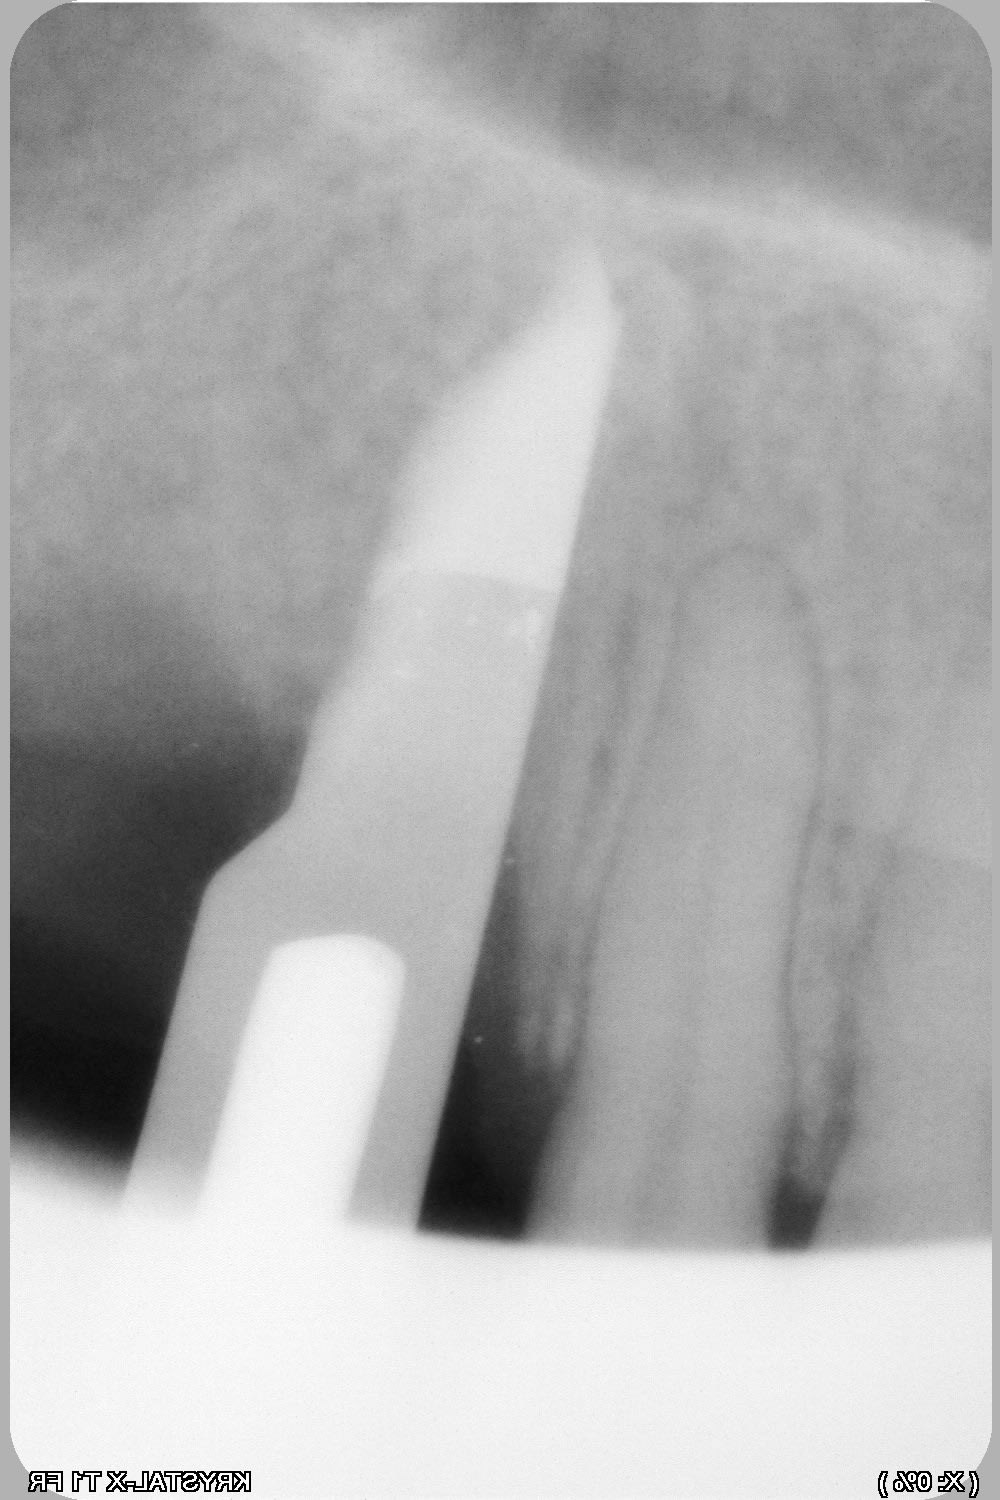

une petite idée du cas, je vais essayer en expansion, puisque c'est mon dada :-)) , et ça permettra de rajouter une vidéo pour pour animer la formation « Expansion Osseuse » à Sallanches les jeudi 4 et vendredi 5 avril 2019 ...

Be ve 23 overview nlkzvu - Eugenol

Be ve 23a 3d muwugo - Eugenol

Be ve123b overview yzsmc3 - Eugenol

Be ver 23 3d sulv8f - Eugenol

Bonjour pour obtenir ton os en vert tu as réalisé une segmentation dans bsp?

c'est pas Blueskyplan....c'est Simplant...